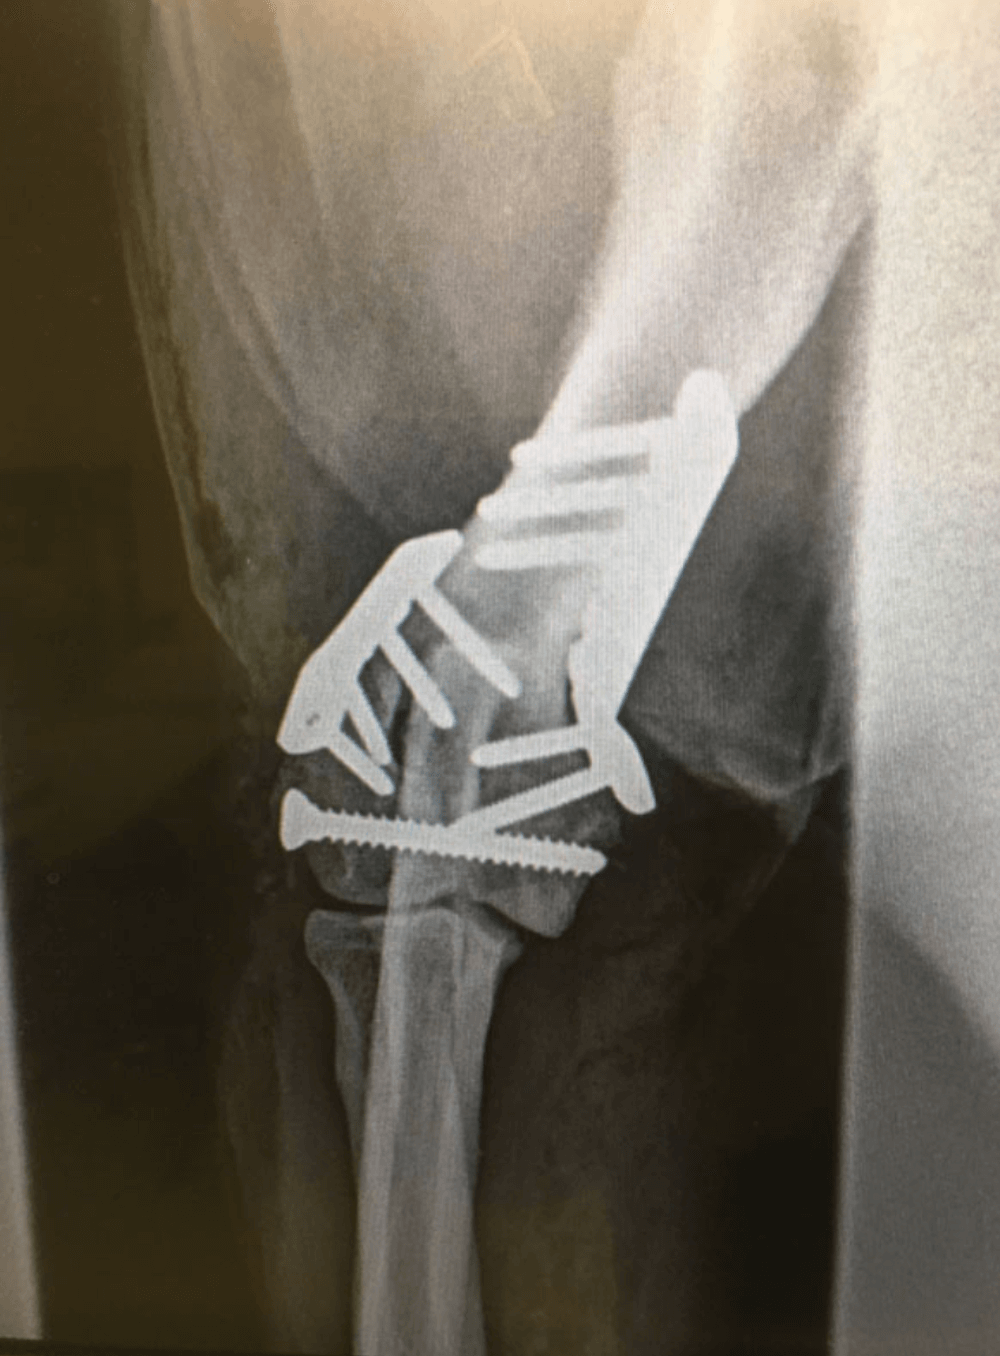

Metatarsal Plating

Example of metatarsal plating.